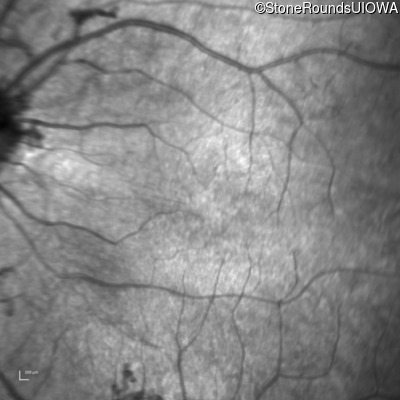

Infrared Fundus Photograph - Right - 20/50 +1

Exemplar

Infrared Fundus Photograph - Left - 20/50 +1